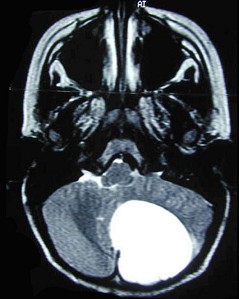

星形细胞瘤(如图所示)的特点 ( ) NSJ-1182.jpg

• A.最常见的颅内胶质瘤

• B.多见于大脑半球,界限清楚

• C.中青年多见

• D.儿童以小脑半球多发

• E.实质性肿瘤手术切除可以根治